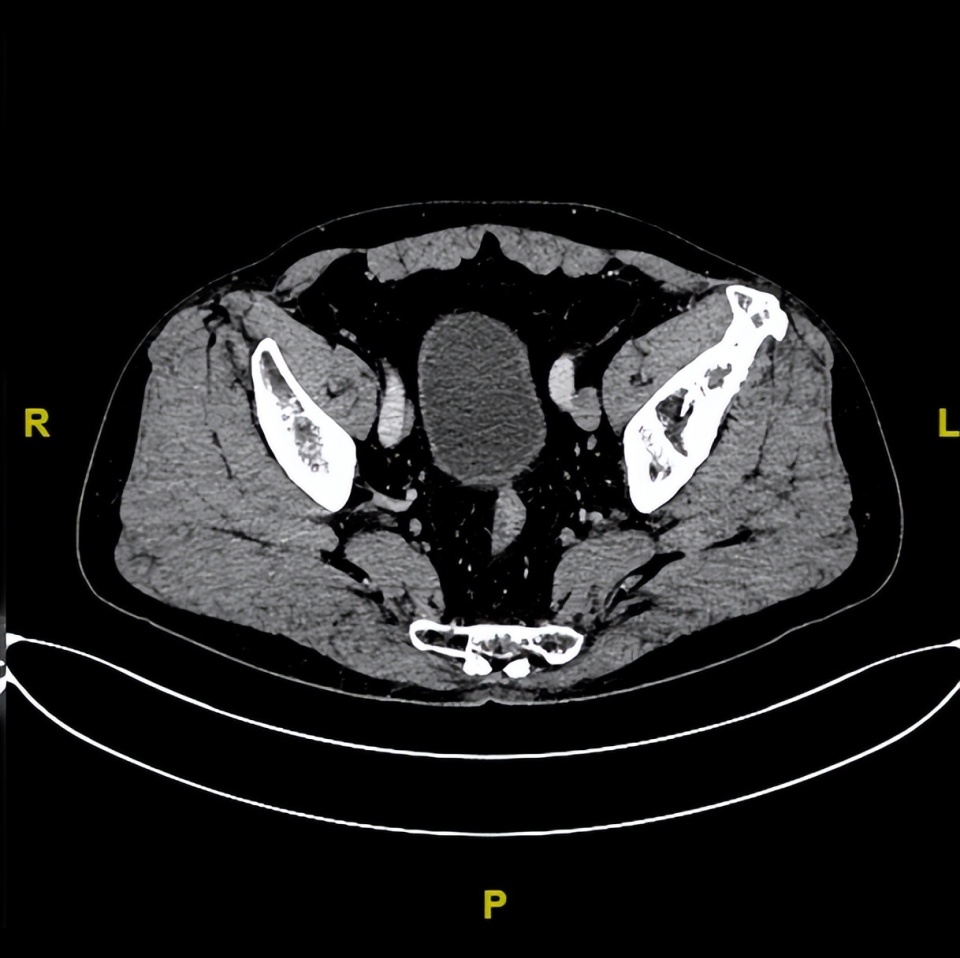

胸部CT(2022-12-13)平扫+增强:双肺转移;左侧髋关节CT:左侧髂骨见片状溶骨性骨质破坏,周围软组织肿胀,考虑骨转移。

基线(2022年12月13日)

△基线胸部CT和盆腔CT髂骨病灶